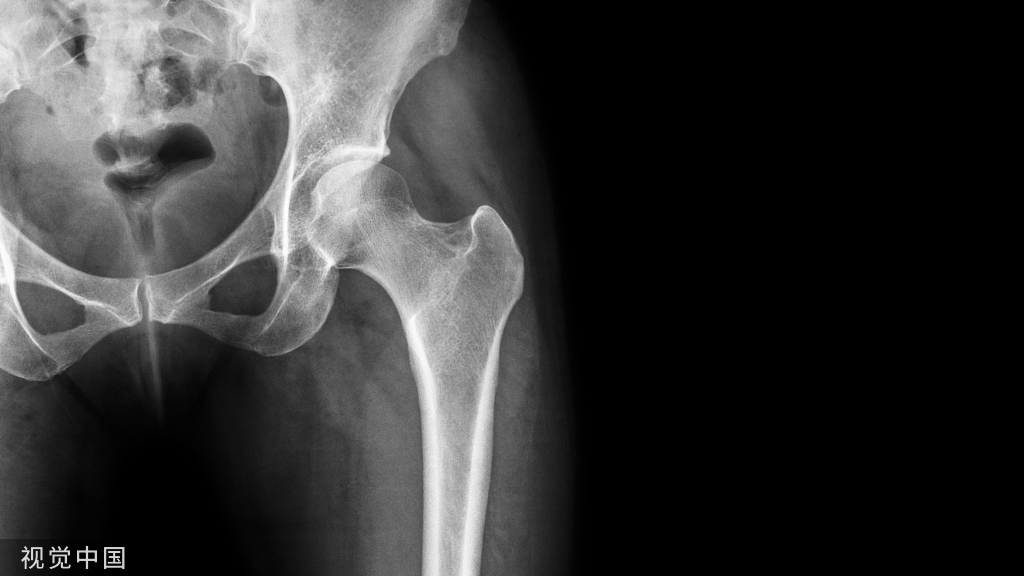

静脉血栓栓塞症是创伤骨科患者的常见并发症,也是导致患者围手术期死亡的主要原因之一。本文讲述了骨科围术期静脉血栓栓塞症的诊治!

静脉血栓栓塞症(VET):是指血液静脉在不正常地凝结,阻塞管腔所致静脉回流障碍性疾病。可发生于全身各部位静脉,以下肢深静脉为多。

深静脉血栓塞形成(DVT):是指血液在深静脉内不正常地凝结,阻塞管腔所致静脉回流障碍性疾病可发生于全身各部位静脉,以下肢深静脉为多。